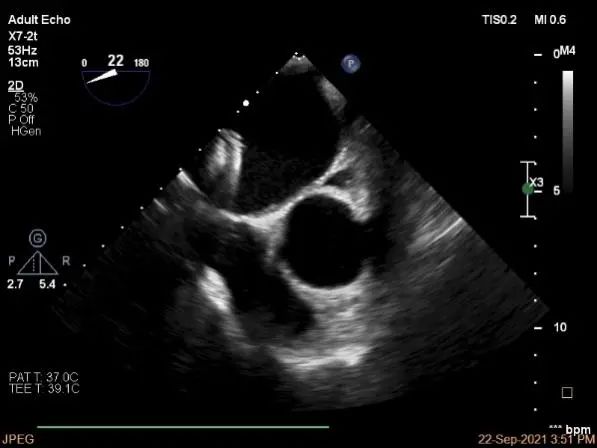

术前超声评估

3D:P1区脱垂并腱索断裂,部分AC受累,Width:11.4mm

3D-color:重度MR,4级